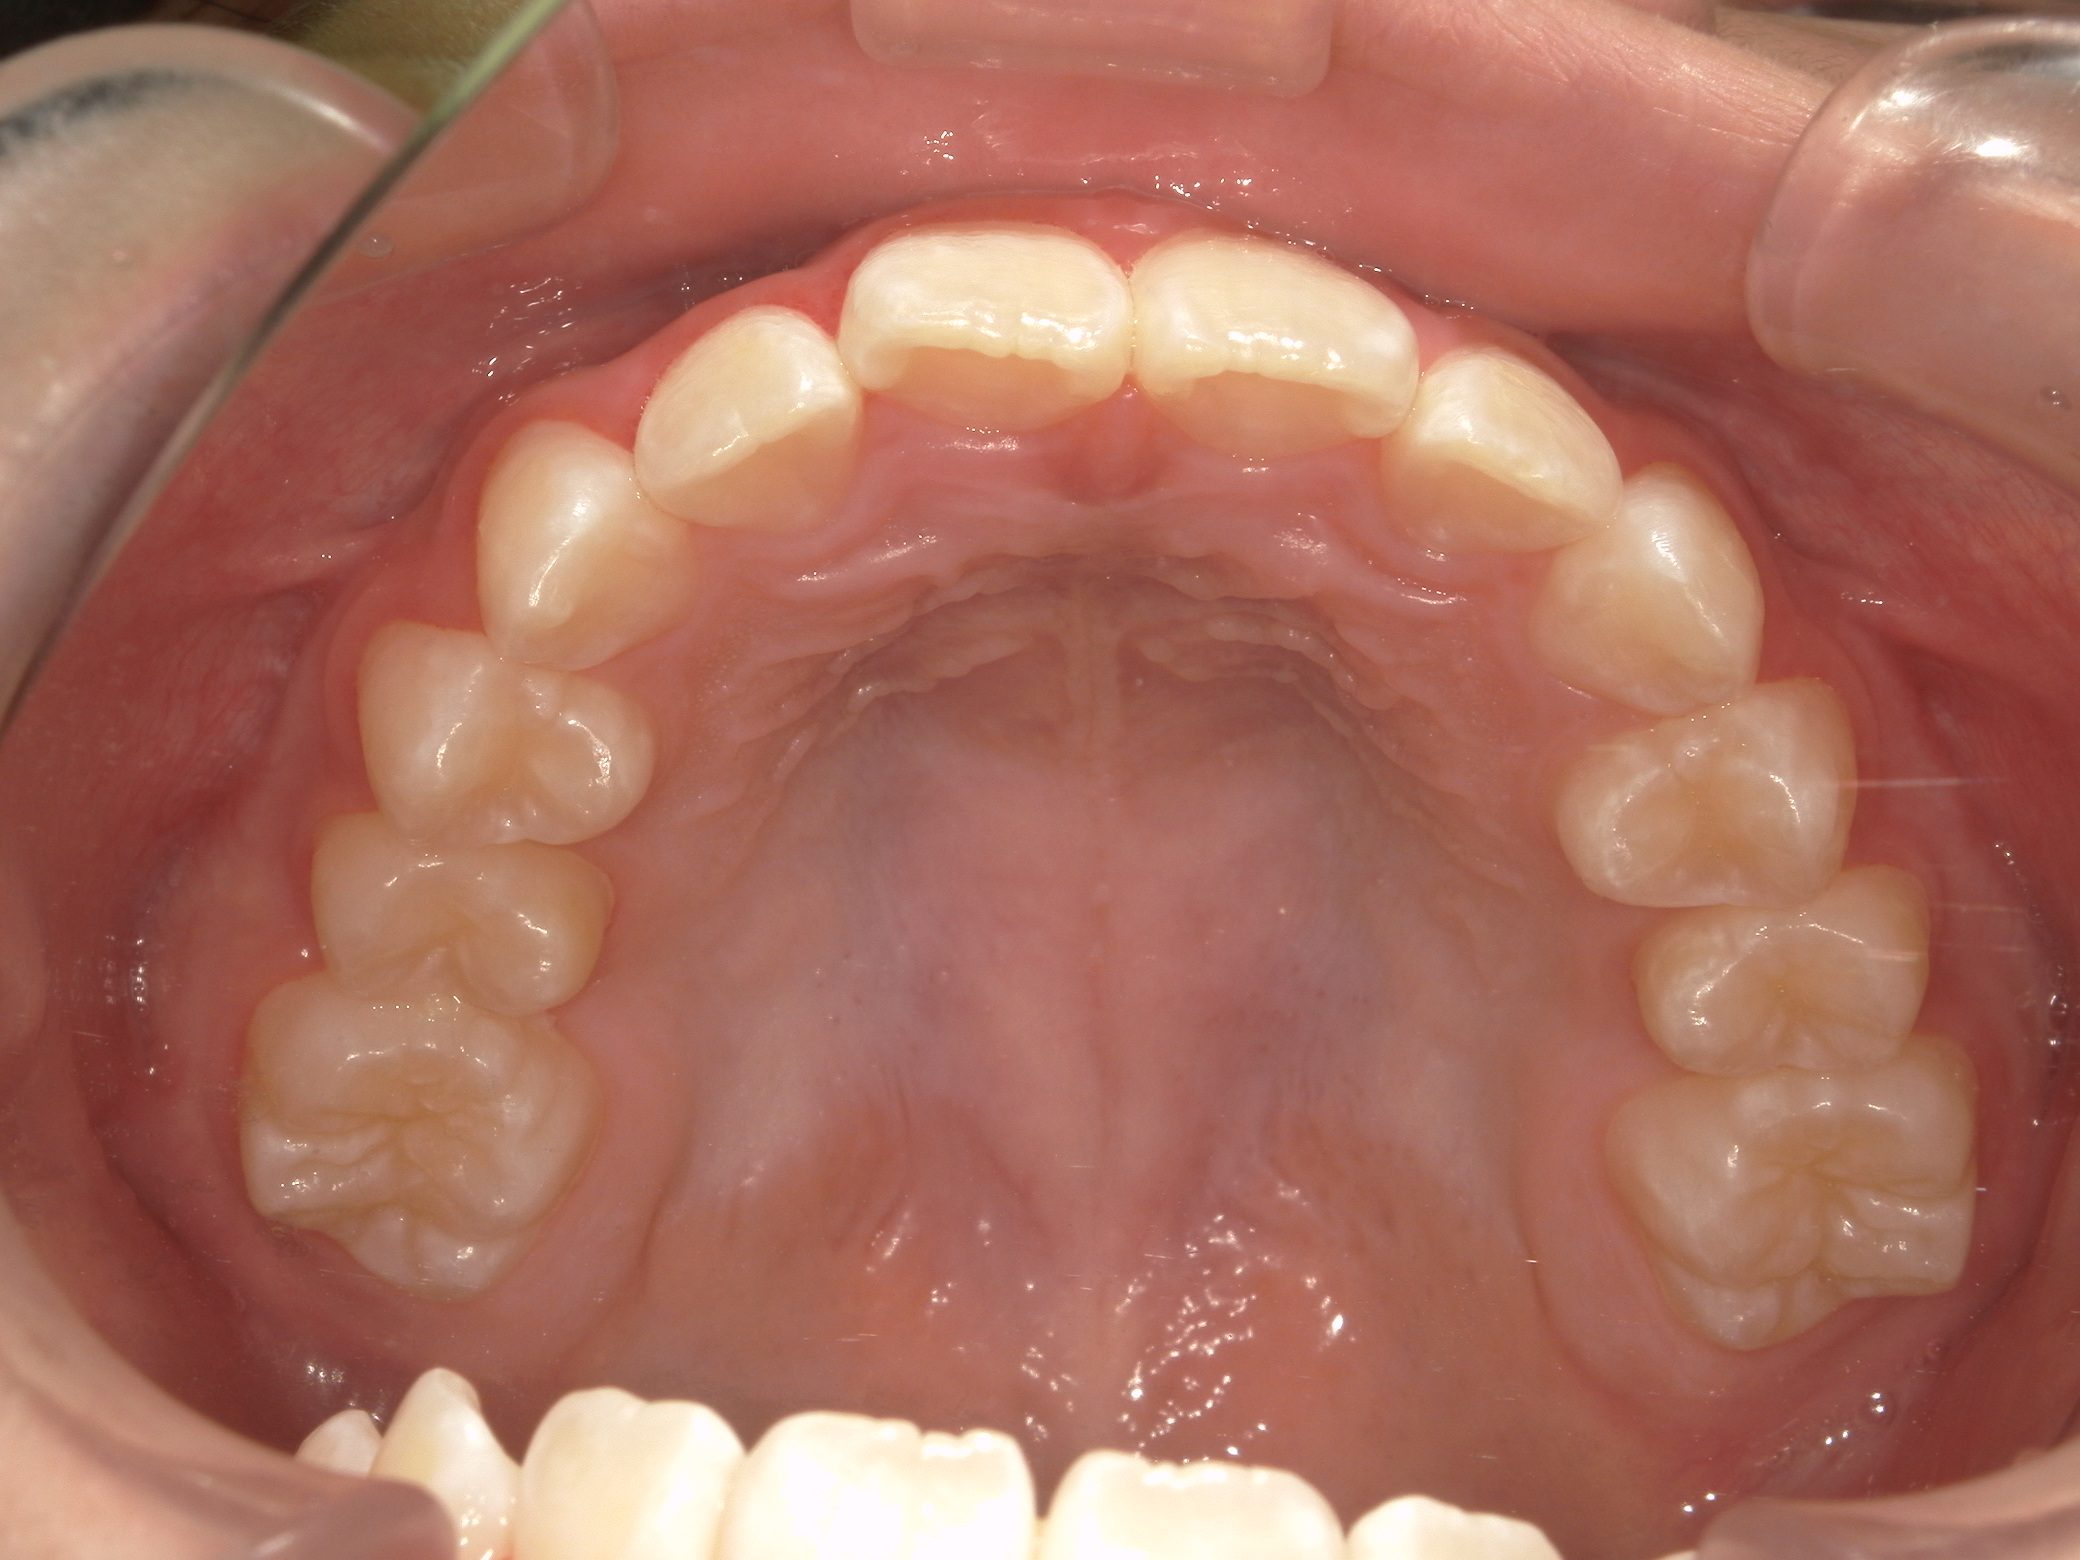

After